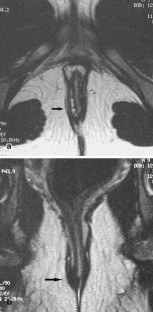

Fig. 2